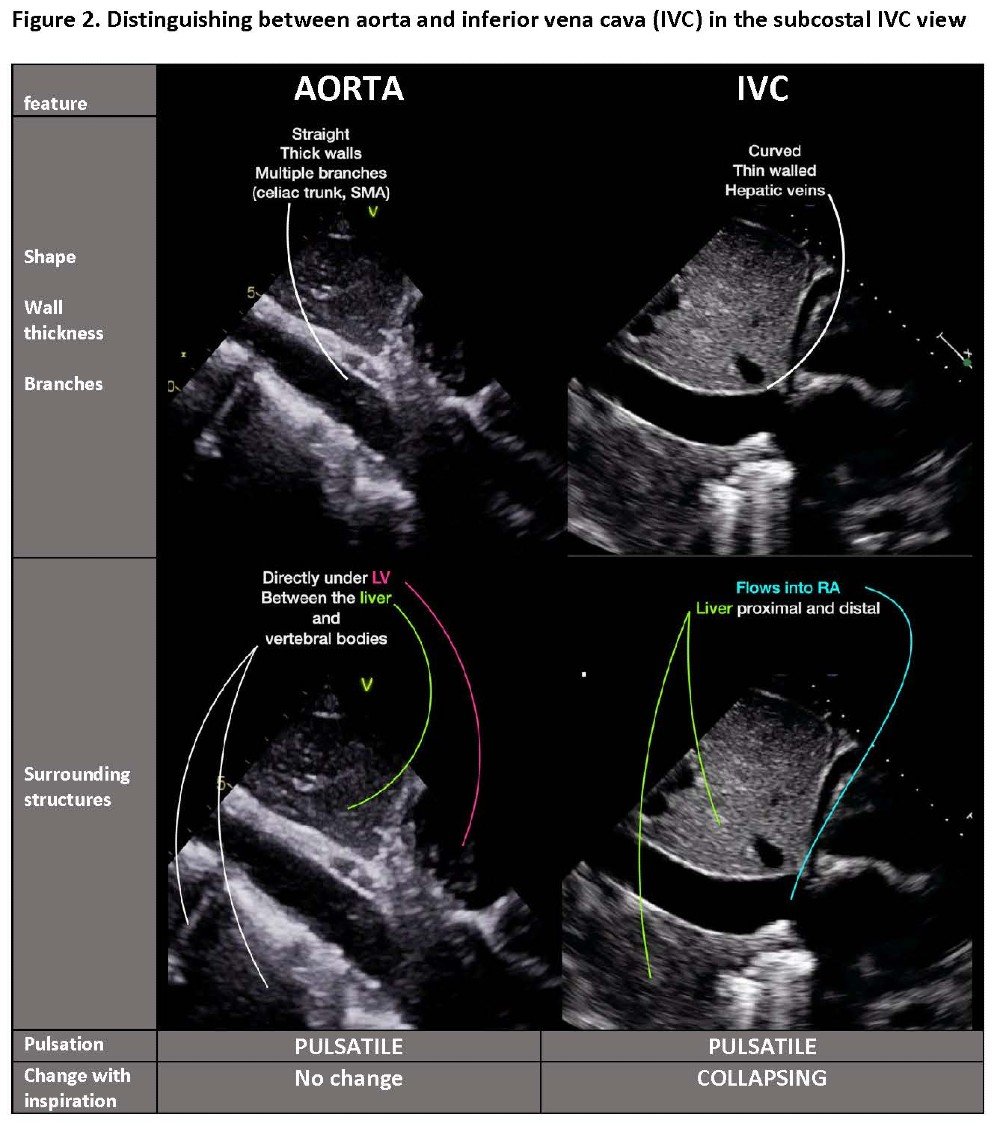

In the subcostal window, insonation is through the liver. The transducer is flat against the abdomen and directed slightly to the left to obtain the subcostal four chamber view (SC4C). In the same window, positioning sagittally midline with the marker pointing toward the patient’s head will show either abdominal aorta or the subcostal view of inferior vena cava (SCIVC). The vessels are parallel: tilting the transducer switches from aorta (left tilt) to IVC (right tilt). (Video 1, Figure 2)

Video 1. Anatomic relationship of abdominal aorta and inferior vena cava – easy imaging of both by tilting of transducer